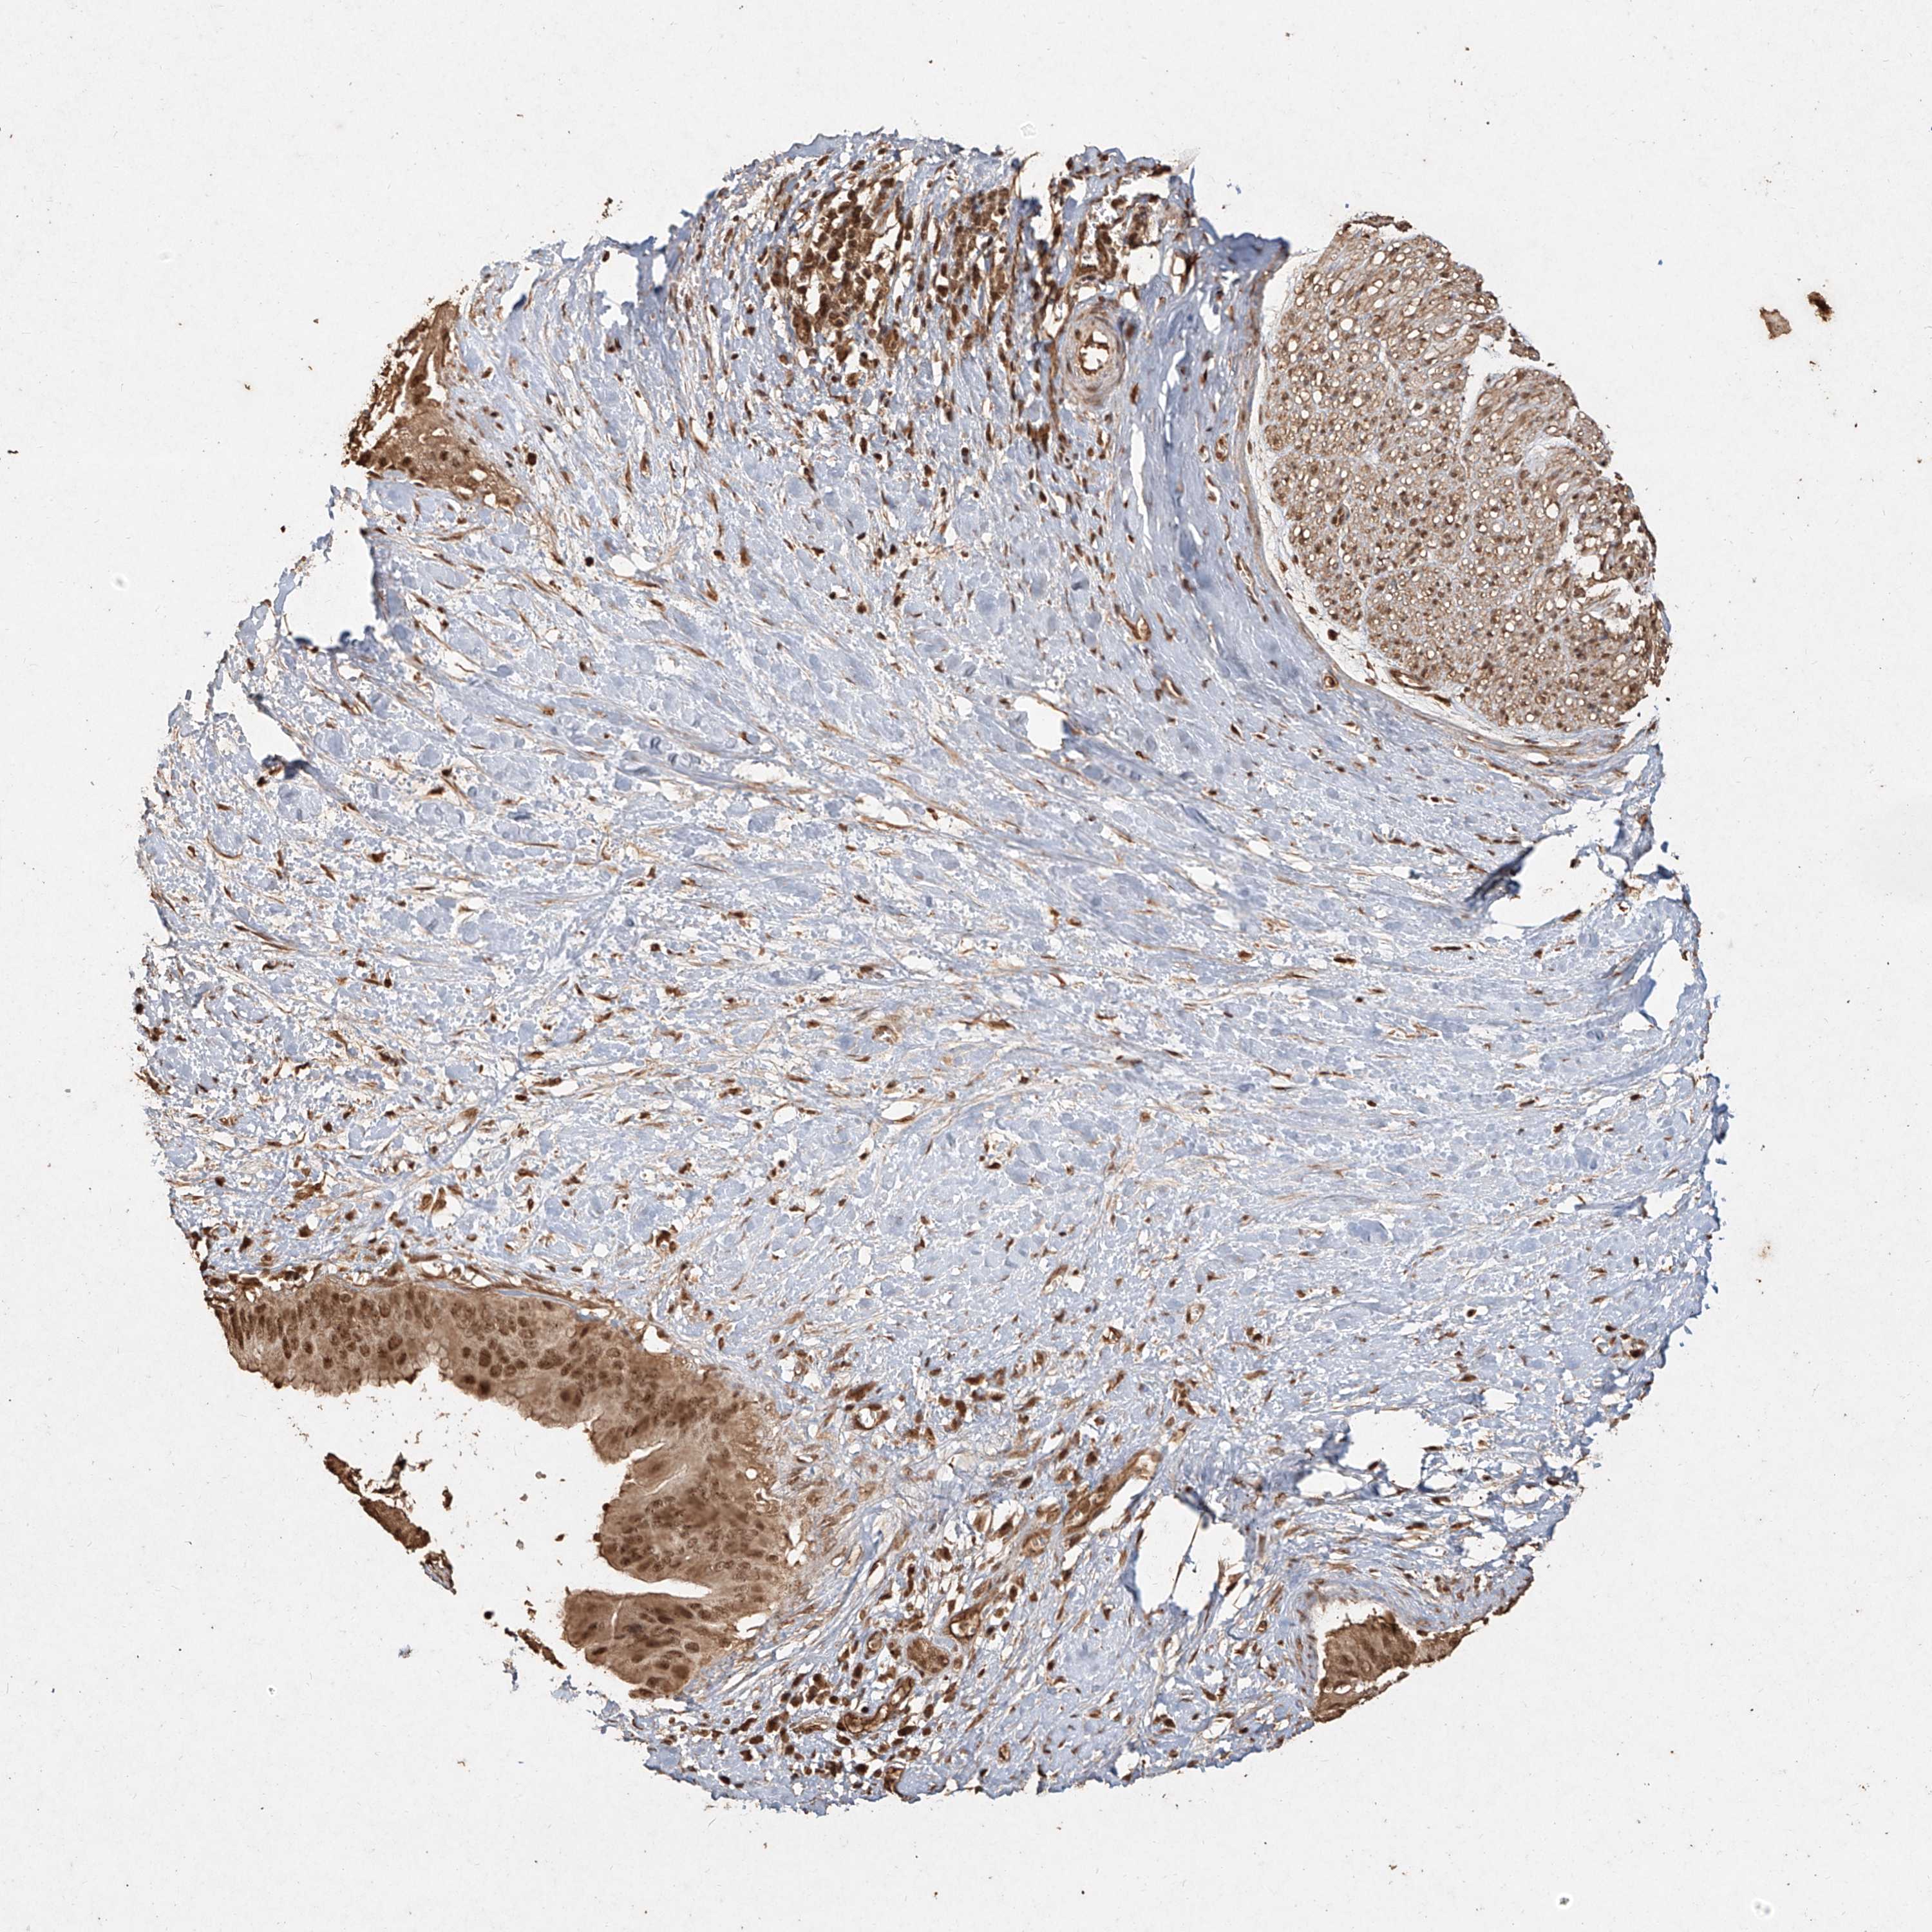

PANCREATIC CANCER - Protein expressioni

A mouse-over function shows sample information and annotation data. Click on an image to view it in a full screen mode. Samples can be filtered based on level of antibody staining by selecting one or several of the following categories: high, medium, low and not detected. The assay and annotation is described here.

Note that samples used for immunohistochemistry by the Human Protein Atlas do not correspond to samples in the TCGA dataset.

Antibody stainingi

Antibody staining in the annotated cell types in the current human tissue is reported as not detected, low, medium, or high, based on conventional immunohistochemistry profiling in selected tissues. This score is based on the combination of the staining intensity and fraction of stained cells.

Each image is clickable and will lead to virtual microscopy that enables deeper exploration of all samples and also displays staining intensity scores, fraction scores and subcellular localization as well as patient and tissue information for each sample.

Antibody HPA028869

Antibody CAB033212

Antibody CAB033515

Staining

High

Medium

Low

Not detected

Intensity

Strong

Moderate

Weak

Negative

Quantity

>75%

75%-25%

<25%

None

Location

Nuclear

Cytoplasmic/membranous

Cytoplasmic/membranous,nuclear

Adenocarcinoma, NOS